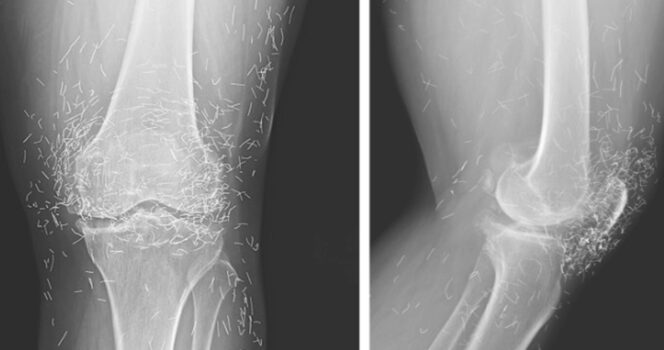

Doctors find “gold mine” in woman’s knees

When a 65-year-old South Korean woman went in for knee pain, doctors weren’t expecting to strike gold. But that’s exactly what they found.

Acupuncture, a centuries-old alternative treatment, involves inserting needles into the body at specific points to relieve pain or treat illnesses. In this case, the needles— presumably made of gold — were intentionally left in her knees for continued stimulation.

He also warned that embedded needles can complicate X-ray readings. “The needles may obscure some of the anatomy,” Guermazi said in 2013.